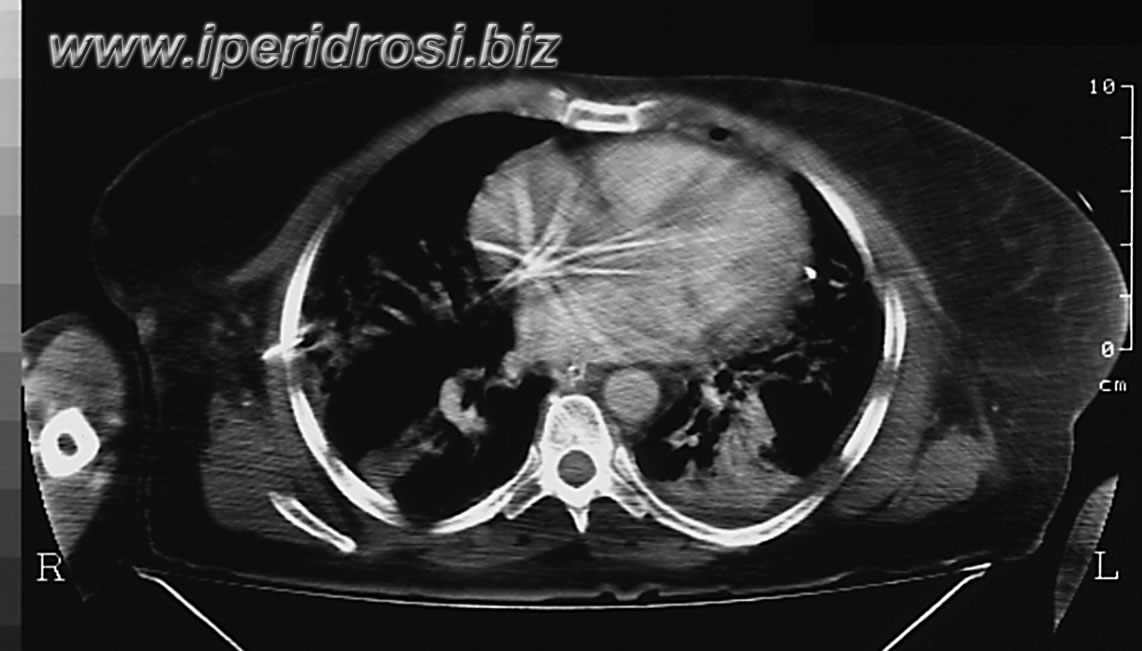

tac del giorno T 5

Al presente controllo si osserva regressione del versamento pleurico sinistro e comparsa di addensamenti interstizio alveolari diffusamente confluenti da ambo i lati. Residua piccola falda liquida peri e sotto epatica. Non falde di gas libero